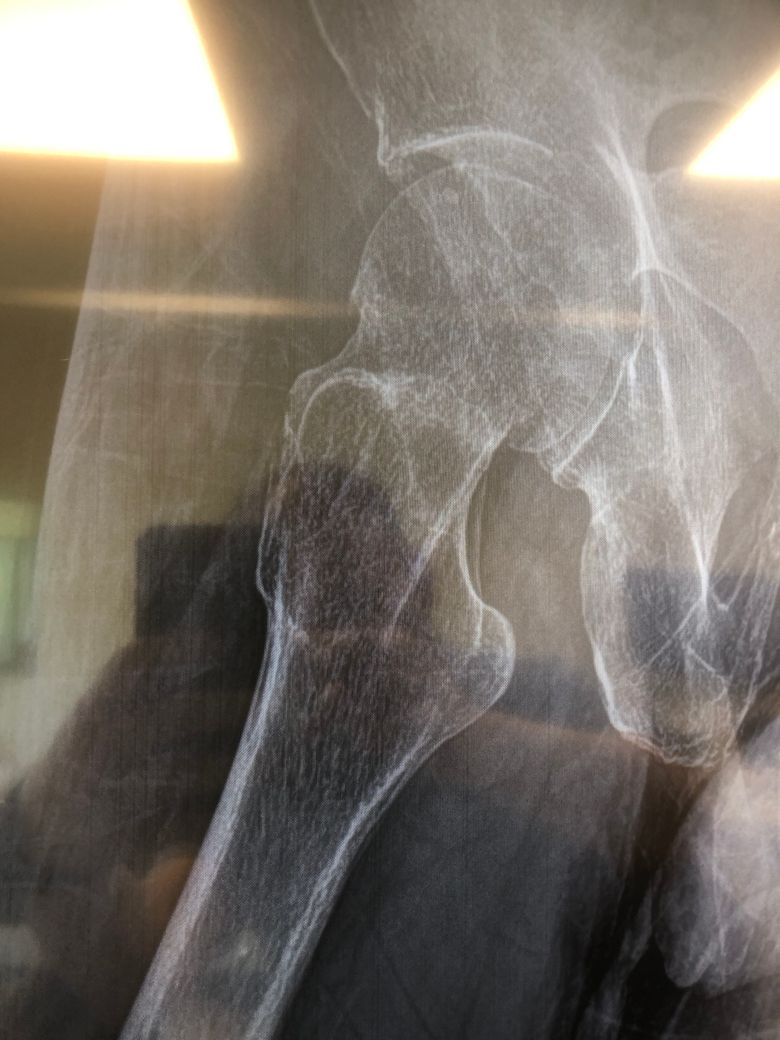

고관절골절이 있었는데 담당의사는 붙었다고 했는데 붙은거 맞나요?

고관절골절 후 수술이 위험할 정도로 몸이 약한 상태라 3개월이상 안정후 매달 X레이를 찍고 담당의사를 만났습니다.

이번달에 담당의사는 골절된 부분이 붙었다고 했는데 붙은게 맞는지 궁금합니다.

올리신 사진 한 장 만 보고 정확하게 파악이 가능하지 않으며 어떻다 말씀드리기는 어렵습니다만, 올리신 사진만 놓고 보자면 뼈가 붙은 것처럼 보이는 것이 맞습니다.

안녕하세요. 강성주 의사입니다.

엑스레이상 아직 금이 남아있는 것으로 보입니다.

하지만 이전 엑스레이와의 비교를 통해 유합여부를 종합적으로 판단하는 것이 필요하겠으며, 정확한 감별을 위해서는 CT촬영을 해보시는 것이 좋겠습니다.